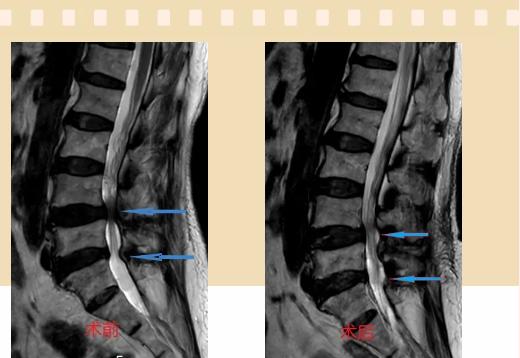

入院后李鵬副主任醫(yī)師為其進(jìn)行了詳細(xì)的查體,完善了術(shù)前的檢查,明確診斷為:腰椎管狹窄癥(L4/5、L5/S1),病人合并2型糖尿病,請內(nèi)分泌科會診,穩(wěn)定血糖后,麻醉科會診病人,排除手術(shù)禁忌,李鵬為病人制定了手術(shù)方案:單側(cè)入路雙側(cè)減壓(ULBD)。

手術(shù)采用三個微創(chuàng)小切口,兩個節(jié)段減壓手術(shù)時間2.5小時,出血50ml。術(shù)后2天腰圍保護(hù)下床活動,術(shù)后5天順利出院。

傳統(tǒng)腰椎管狹窄癥的手術(shù)治療,往往需要切開減壓,同時需要內(nèi)固定融合術(shù),創(chuàng)傷很大,同時可能需要輸血,臥床時間較長,病人合并糖尿病,感染風(fēng)險也高,而本次采用的UBE-ULBD手術(shù)切口更小(加起來約3cm,如果是單節(jié)段狹窄只需要不到2cm切口)、創(chuàng)傷更小,術(shù)后恢復(fù)較快,可以更早地恢復(fù)正常活動。

此外,手術(shù)保留了病變節(jié)段的穩(wěn)定性,是一種微創(chuàng)的椎管減壓手術(shù),能通過切除部分椎板、關(guān)節(jié)突關(guān)節(jié)、黃韌帶來解除神經(jīng)根和硬膜囊的壓迫,不需要額外行腰椎內(nèi)固定術(shù),不需要螺釘及融合器的植入,病人術(shù)后腰椎的活動度不受影響。(盧   闖  劉   旭   袁錦鈺)